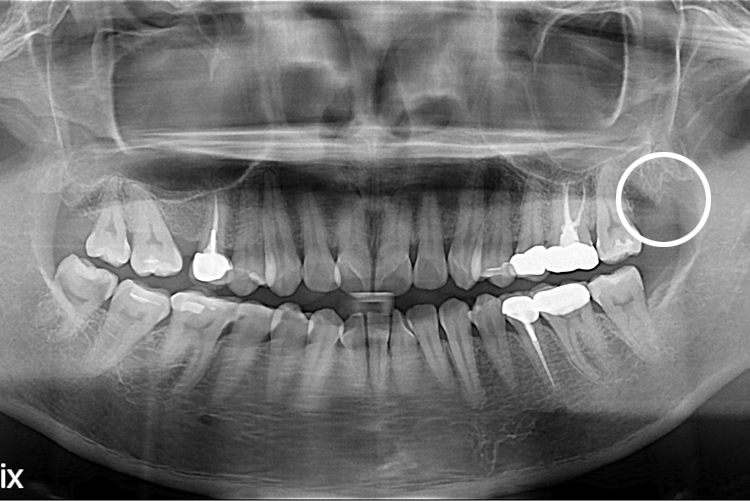

[사랑니] 단순매복 사랑니 발치

치료후 : 2020-11-25

세종치과는 구강악안면외과학 박사이신 원장님이 발치하는 치과 입니다.